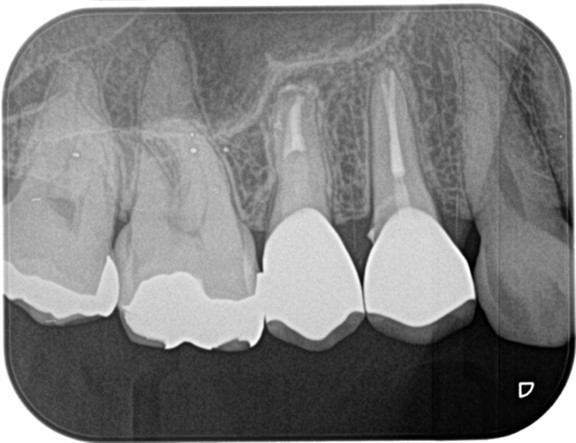

精密根管治療終了後、3ヶ月間仮歯で症状の経過を確認し、予後良好と判断して最終補綴物へ移行しました。

経過2年の段階で根尖に確認できた根尖性歯周炎は縮小し、予後良好の経緯を確認しています。